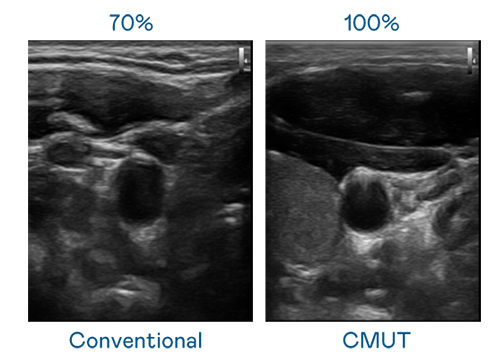

CMUT 技术是一种用电容式微机电元件来产生超音波讯号的技术。与传统 PZT 压电式技术相比,CMUT 频宽增加 30%,更宽频的超音波讯号让影像解析度大幅提升,是实现高影像品质医疗超音波扫描、促进精准医疗发展的关键技术。

大频宽带来超清晰影像

超音波影像的解析度高低,首先取决于探头能发出的讯号频宽。熊猫体育「中国」 CMUT 可提供高清晰的超音波讯号,提供高频宽、高灵敏度、影像纹理细节更高的超音波影像,协助医护人员缩短影像判读时间及利用精准的医疗影像进行诊断。